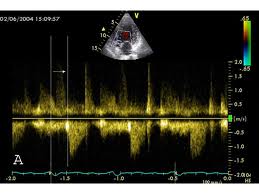

- Echo Lab (2D Echo, Doppler Echo, TEE Lab, Dobutamine Echo, Stress Echo)

This test is used to determine if you have obstructed coronary arteries that may cause you to be experiencing chest pains. This condition may lead you to sustain a heart attack. This especially useful for people experiencing chest pain. Echocardiography is a diagnostic test that uses ultrasound waves to create an image of the heart muscle. Ultrasound waves that rebound or echo off the heart can show the size, shape, and movement of the heart's valves and chambers as well as the flow of blood through the heart. Echocardiography may show such abnormalities as poorly functioning heart valves or damage to the heart tissue from a past heart attack.

This test is especially useful in evaluating patients who are experiencing chest pain or shortness of breath. This may help diagnose a cardiac condition such as heart failure as the cause of the patients symptoms. Endovenous ablation is a minimally-invasive procedure that uses a catheter inserted into a vein to direct heat from laser optics or a radiofrequency electrode. This heat shrinks varicose veins and cuts off their blood supply.